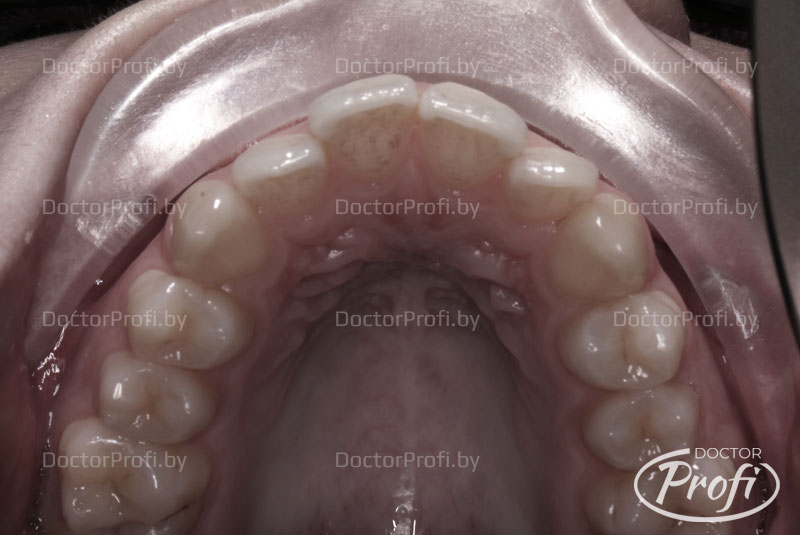

Пациентка, Дарья, 18 лет, жалобы на эстетику зубного ряда — сужение и укорочение верхнего зубного ряда, повороты зубов, скученность, эстетический недостаток.

Срок лечения составил 8 месяцев. В результате проведенного лечения выполнено расширение зубного ряда, выравнивание зубов, получили хорошее функциональное и эстетическое состояние.

После